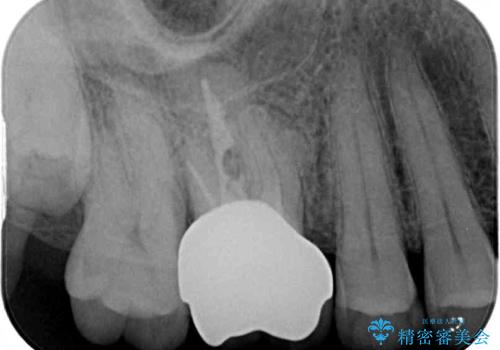

歯周外科処置を併用した奥歯の補綴治療

- クラウンが装着された奥歯から、歯磨きの度に出血するとのことで来院された患者様です。

虫歯が歯肉の奥深くにまで及んでおり、歯肉が腫れやすい状態となっていたため、歯肉の切除並びに歯槽骨の形態修正を行い、虫歯が歯肉の外に出てくるようにした上で、オールセラミックにて補綴することとしました。

歯間ブラシを通す度に出血をするのは、ご自身の磨き方が悪いからと思っていらっしゃいましたが、治療後は全く出血することがなくなり、患者様には大変満足していただきました。